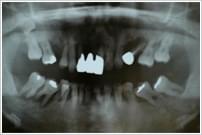

インプラント埋入後

口腔内写真